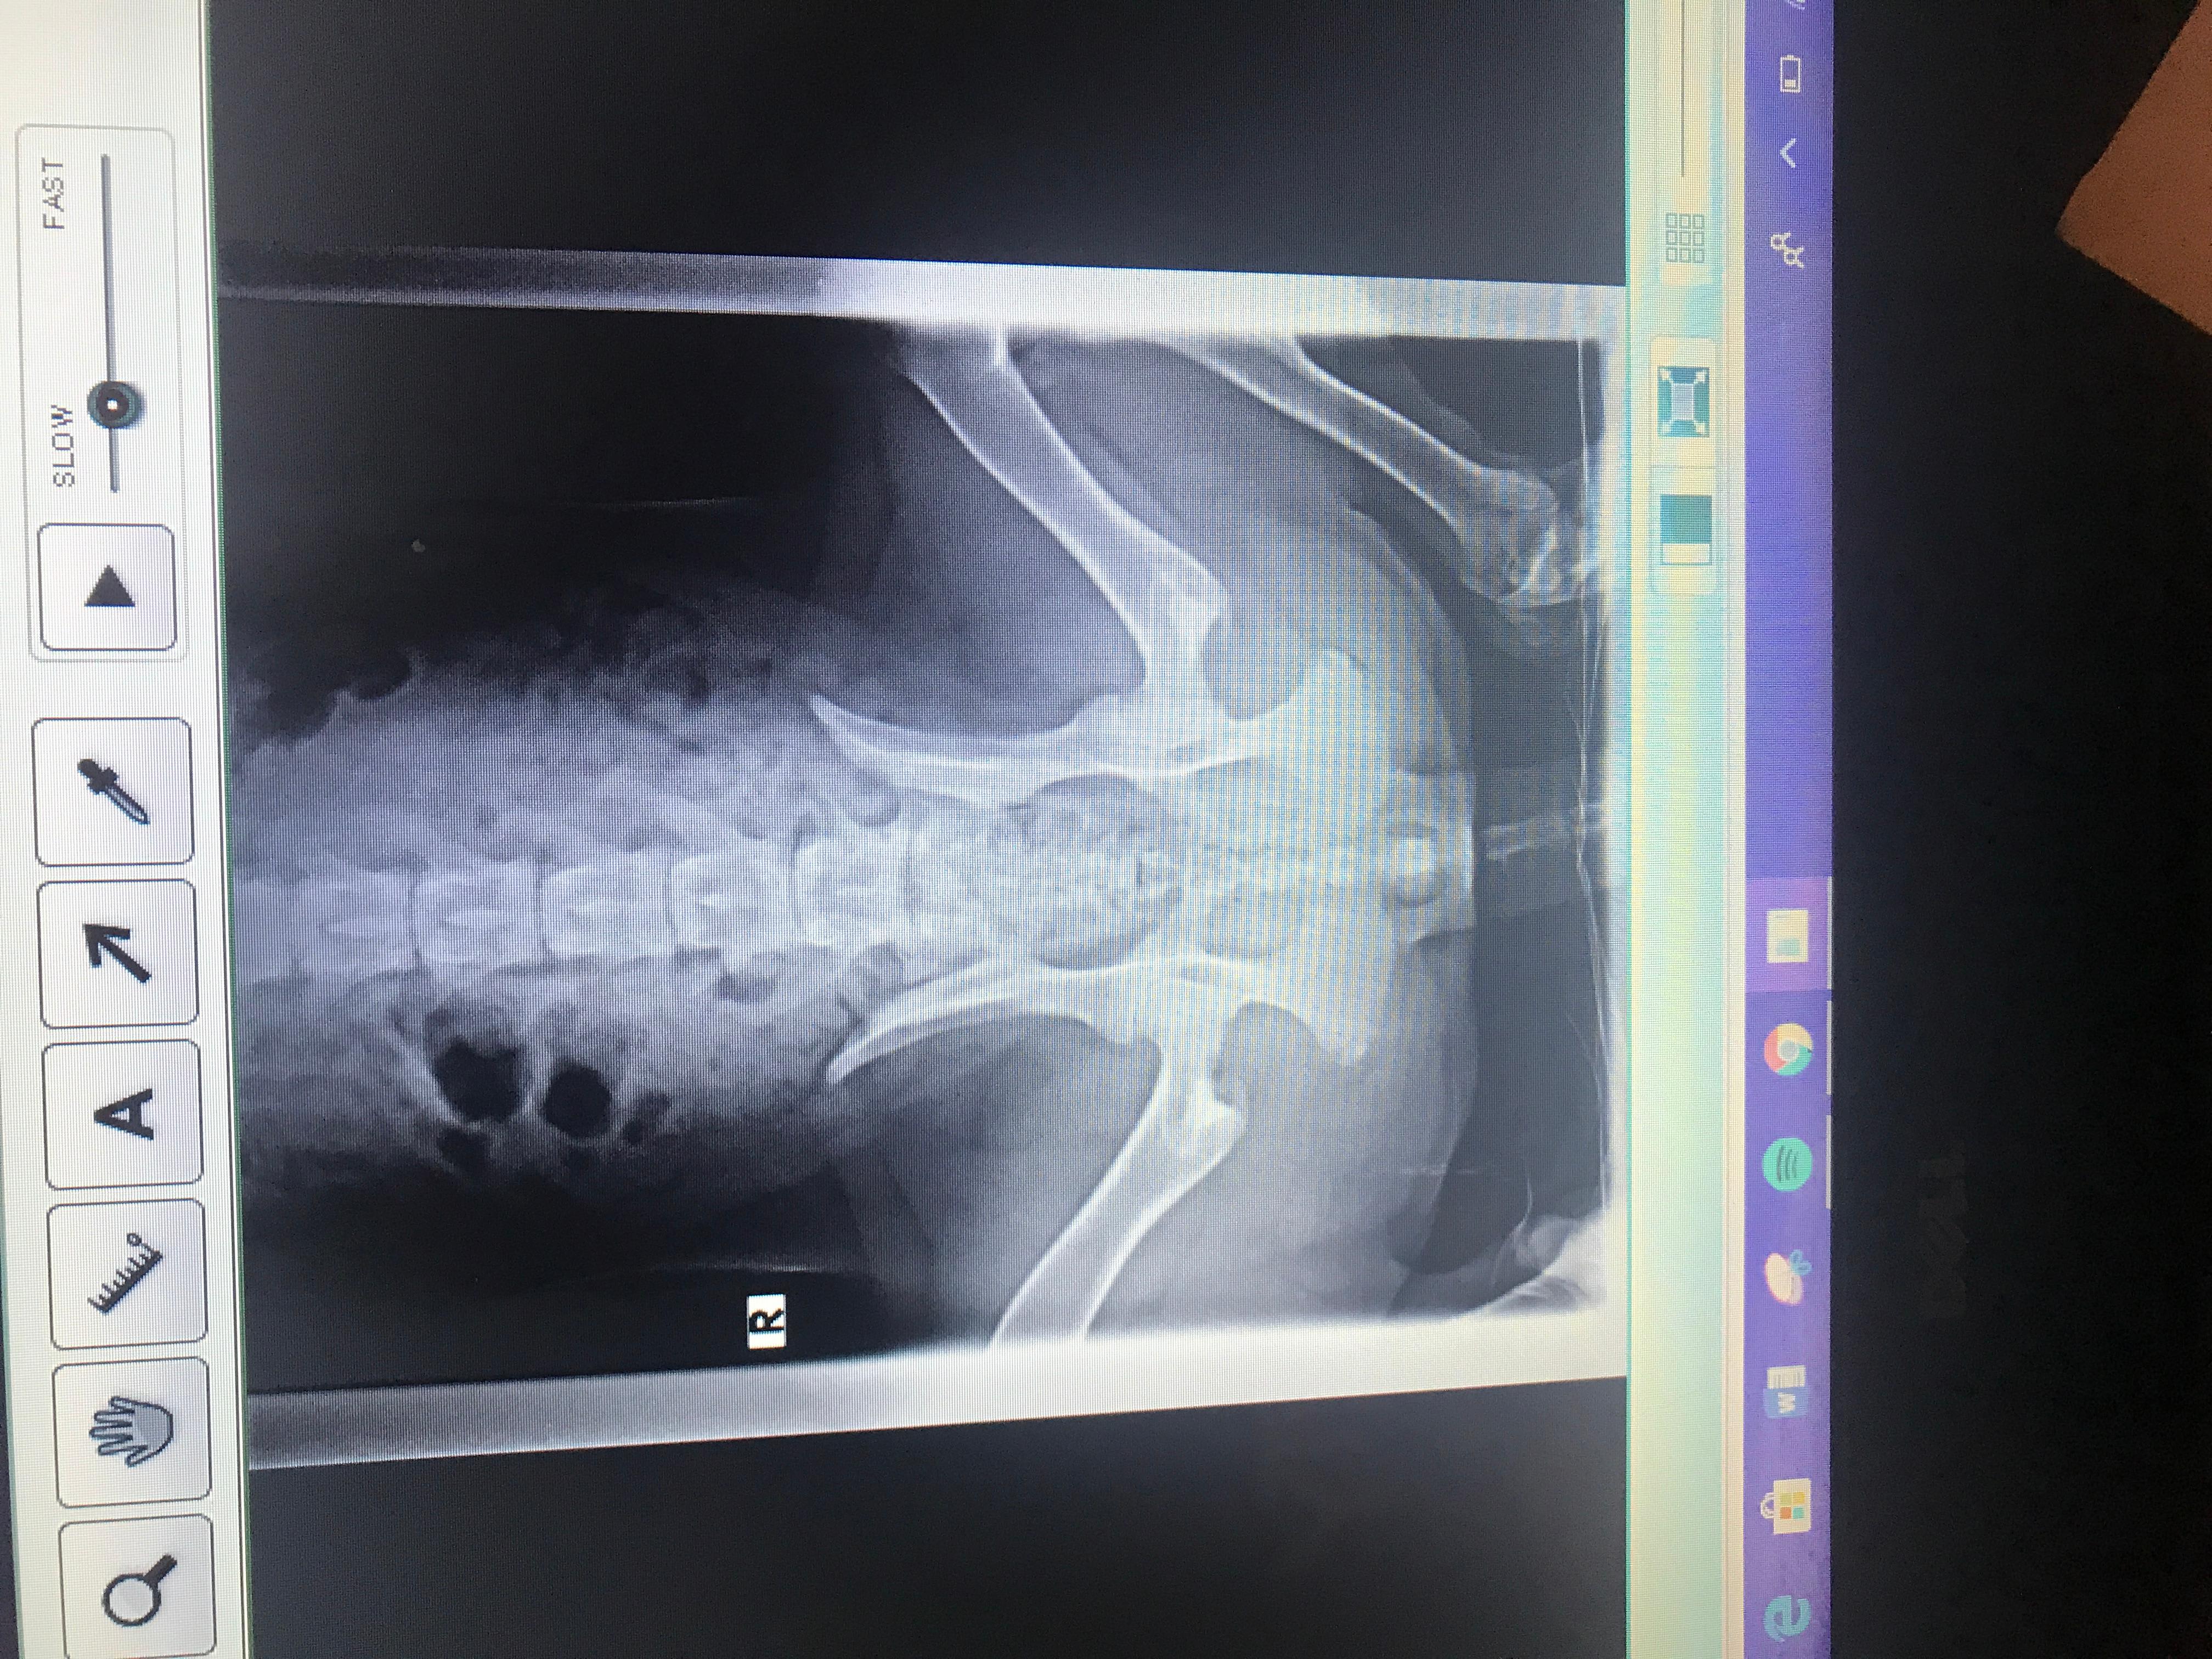

Pet's info: Dog | German Shepherd | Female | unspayed | 6 months and 2 days old | 41 lbs

I need a second opinion. Does my 6 month German Shepherd female have a hip problem? She has a hard time getting up and sometimes doesn’t want to walk

Bella can definitely have hip problems with her symptoms. With the X-rays provided it is not the most appropriate way to determine hip dysplasia. The best X-rays are sedated X-rays with the hind legs being extended straight and tilted slightly in. I would recommend when you spay her Bella you have them X-ray her hips at the same time to determine this. Once you have these X-rays if hip dysplasia is found, you can talk to a surgeon to find out what is the next step for Bella. Here is a link to a photo that shows you how the legs should be to evaluate hips. http://www.azpetscan.com/uploads/2/3/8/3/23831955/8701405.jpg?377 Thank you for using PetCoach.